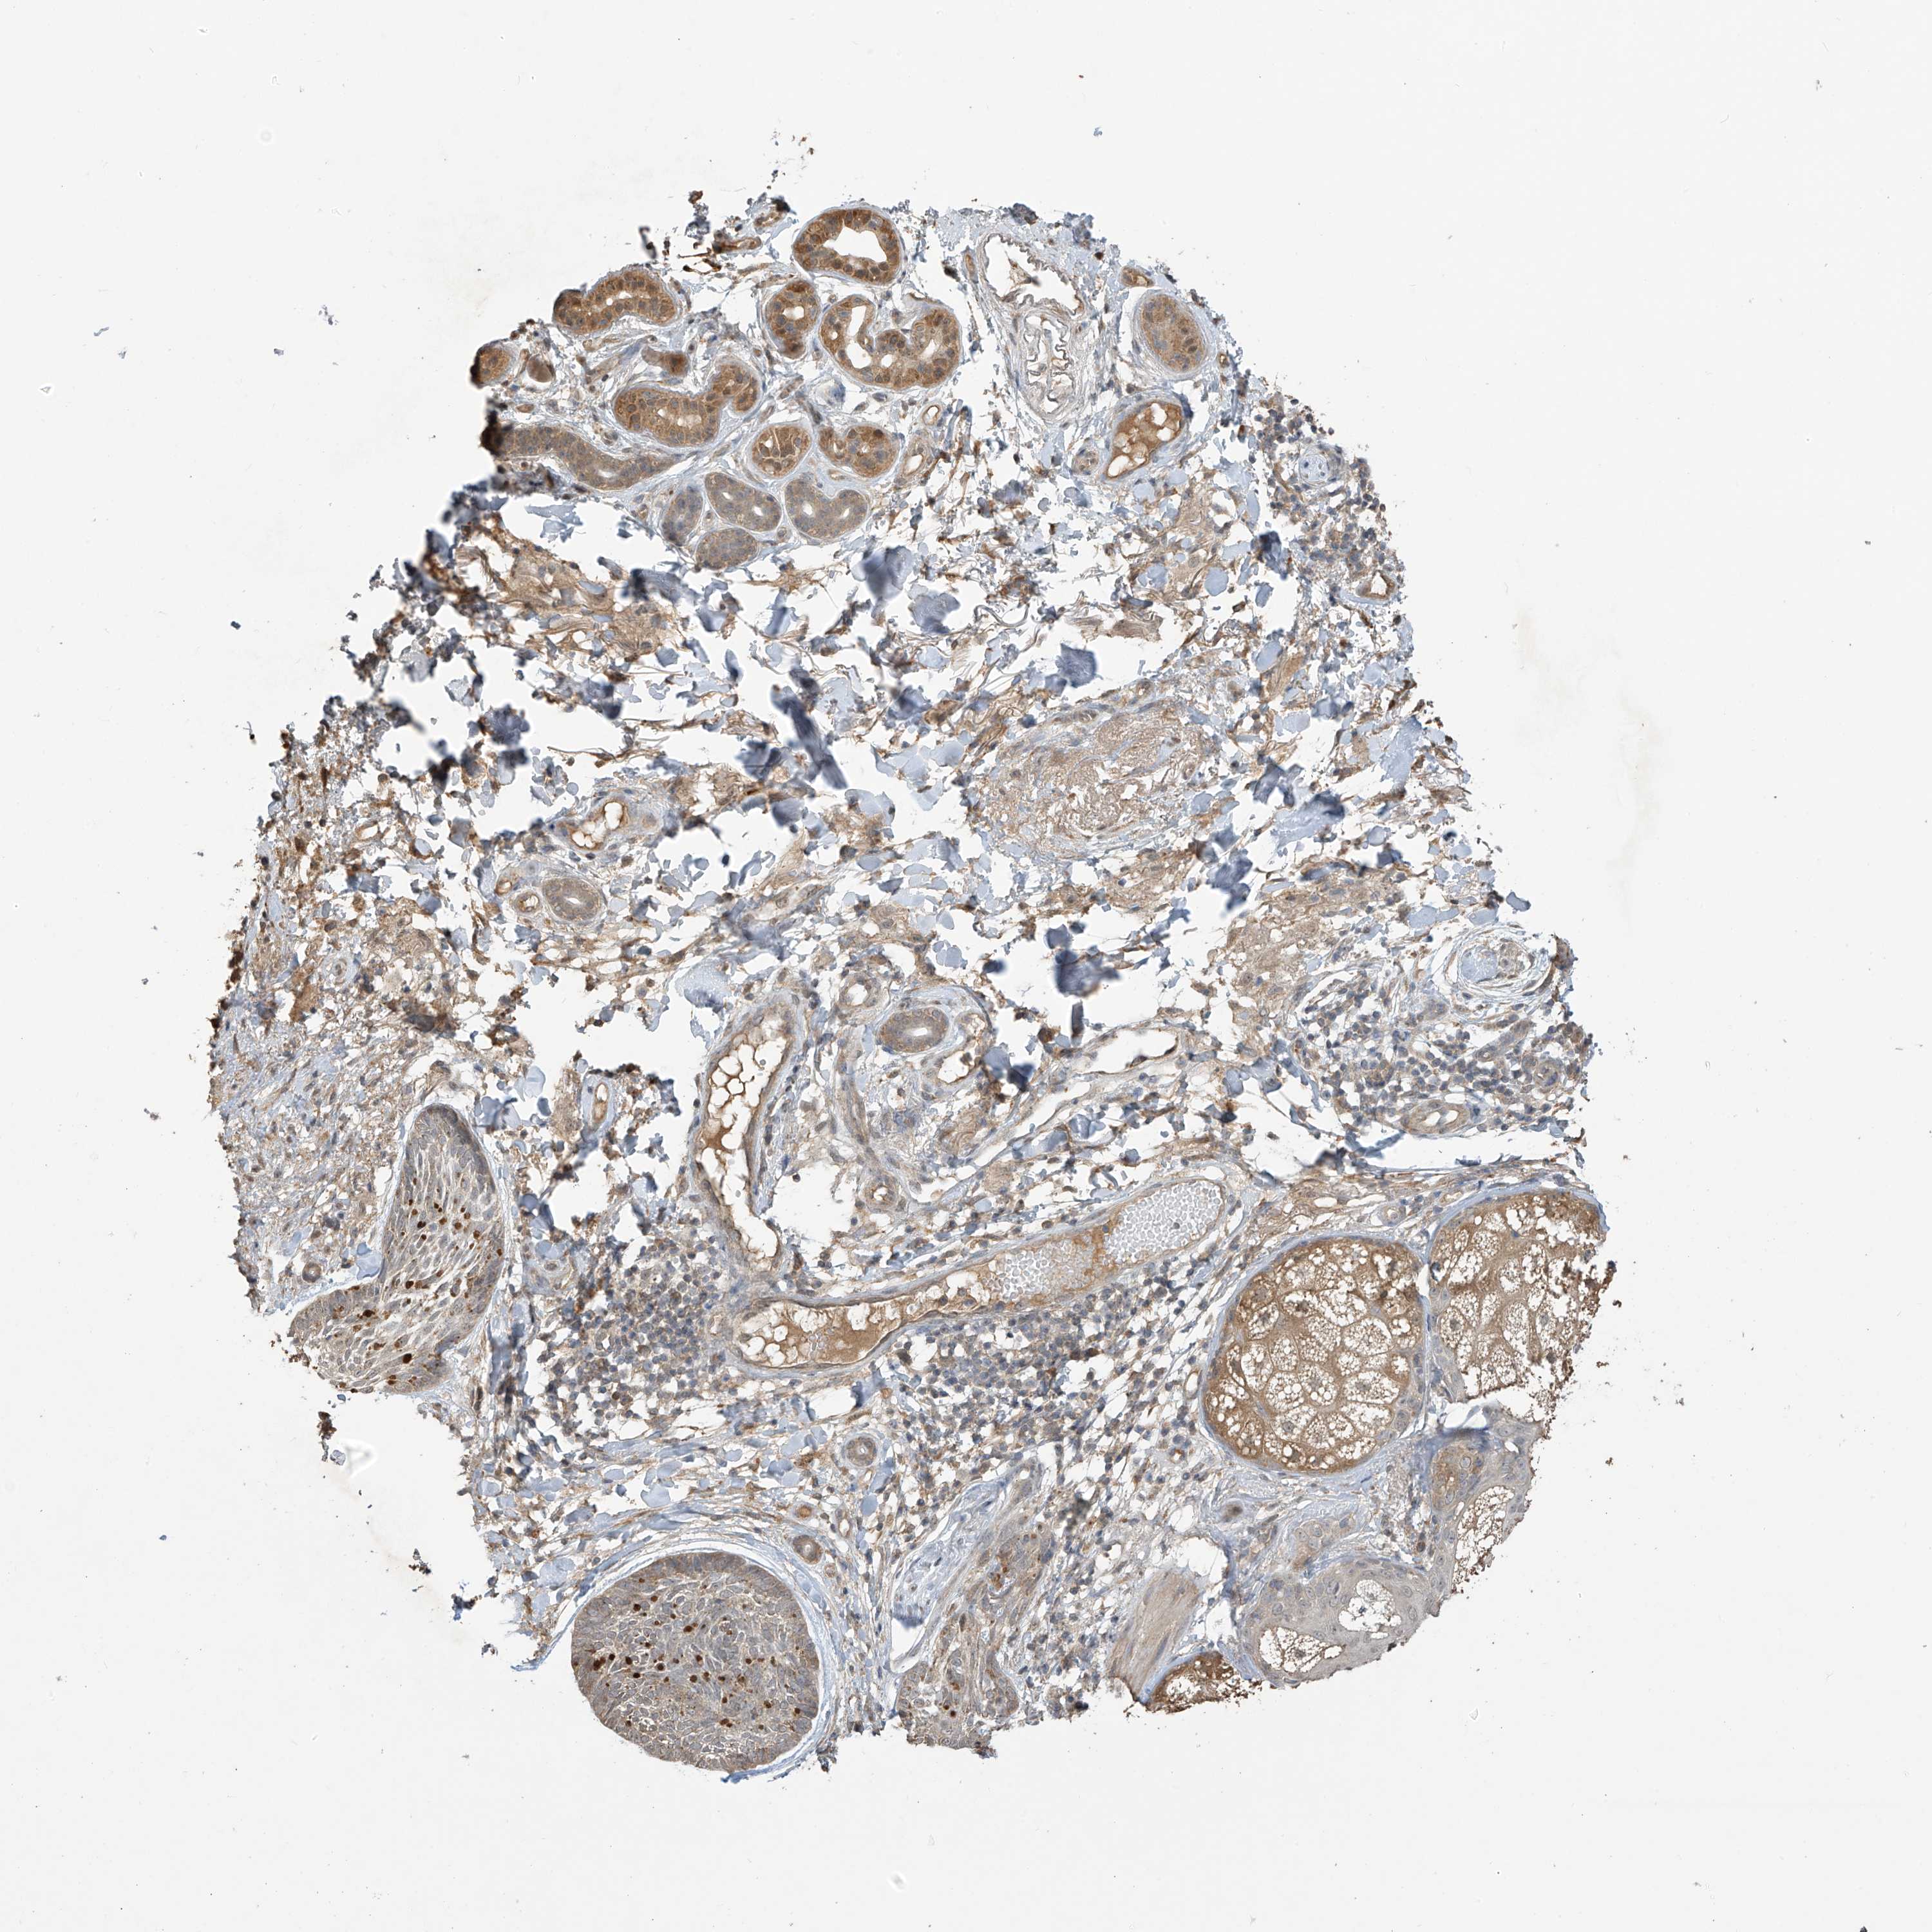

SKIN CANCER - Protein expressioni

A mouse-over function shows sample information and annotation data. Click on an image to view it in a full screen mode. Samples can be filtered based on level of antibody staining by selecting one or several of the following categories: high, medium, low and not detected. The assay and annotation is described here.

Antibody stainingi

Antibody staining in the annotated cell types in the current human tissue is reported as not detected, low, medium, or high, based on conventional immunohistochemistry profiling in selected tissues. This score is based on the combination of the staining intensity and fraction of stained cells.

Each image is clickable and will lead to virtual microscopy that enables deeper exploration of all samples and also displays staining intensity scores, fraction scores and subcellular localization as well as patient and tissue information for each sample.

Antibody HPA022994

Antibody HPA023065

Basal cell carcinoma